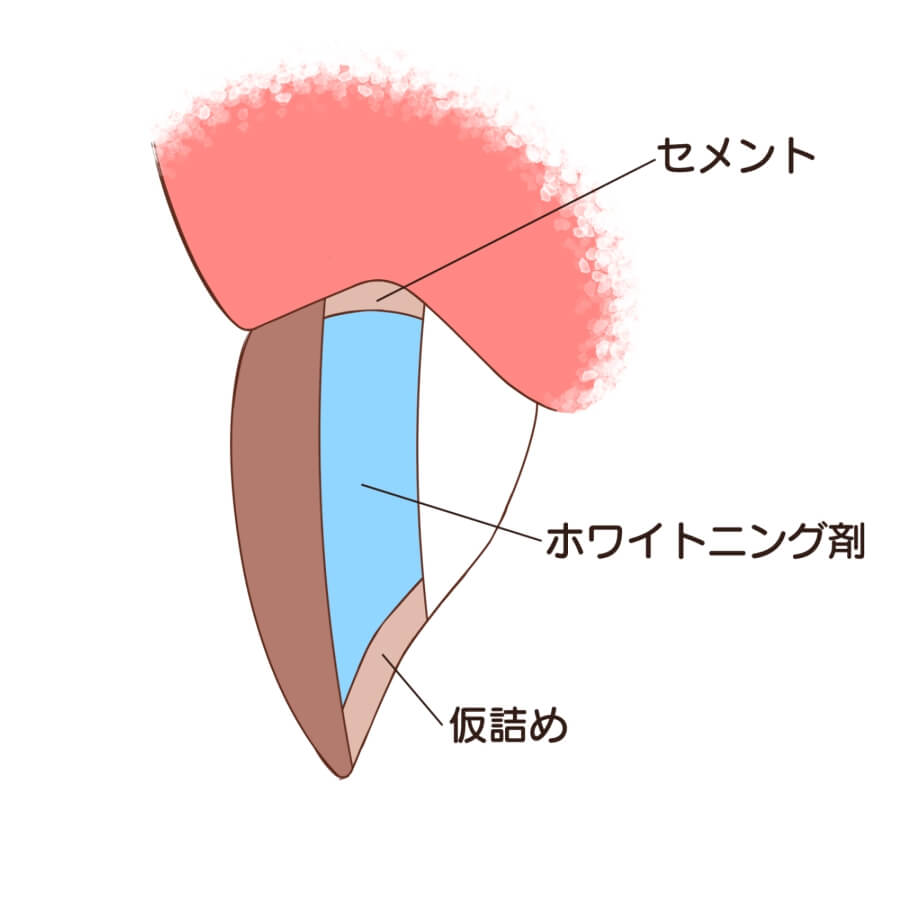

4-3 インターナルブリーチ(パワーブリーチ)

パワーブリーチ法

神経がない歯を白くするオフィスホワイトニング。歯に負担がかからずに白くすることができます。

効果が高いホワイトニングと組み合わせることで1回で白くすることも可能です。

費用:1本10,000円~20,000円

パワーブリーチのメリット

・ウォーキングブリーチと異なり、歯の根や骨に影響がありません。

・神経がない歯でも白くすることができます。

・他の効果の高いホワイトニングと併用して行うことができます。

パワーブリーチのデメリット

・単独でパワーブリーチを行う場合は、回数がかかってしまう場合があります。

・神経がある歯や神経の治療が不完全な歯などはできません。

・パワーブリーチを行う歯の裏側に矯正後の固定式のリテーナーが付いている場合はパワーブリーチができません。